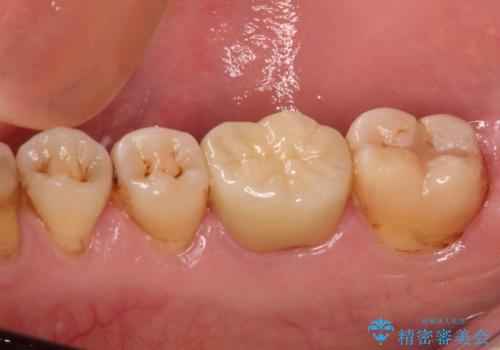

フルジルコニアクラウンは、やや光沢のある材質ですが、奥歯に装着した場合にはさほど気にならず、自然な口元の印象となりました。